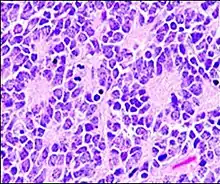

Micrograph of an ameloblastoma showing characteristic palisading. H&E stain.

In histopathology, a palisade is a single layer of relatively long cells, arranged loosely perpendicular to a surface and parallel to each other.[1] A rosette is a palisade in a halo or spoke-and-wheel arrangement, surrounding a central core or hub.[2] A pseudorosette is a perivascular radial arrangement of neoplastic cells around a small blood vessel.[2]

Palisades that are generally longer than a rosette or pseudorosette can be seen in neural tumors such as Schwannoma,[16][17] as well as in ameloblastomas. It can also be seen in nodular basal-cell carcinomas.[18]